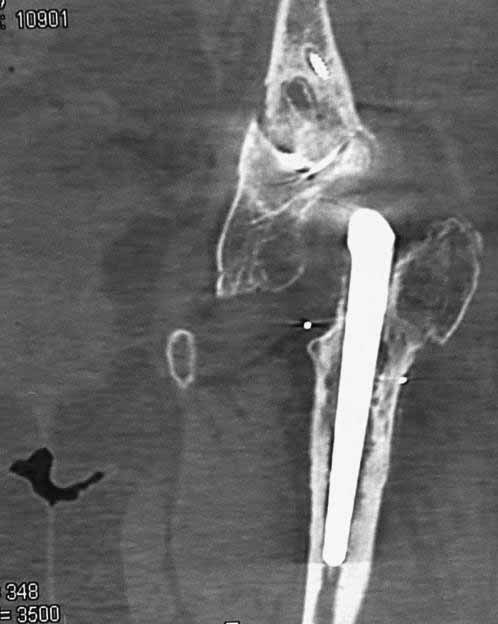

Пациентка 45 лет. Бесцементное эндопротезирование левого тазобедренного сустава 6 лет назад (впадина RM, Mathys, металл-металл, ножка Зульцеровская). За 10 лет до протезирования – коррегирующая остеотомия бедренной кости, которая не срослась в течение года до удаления пластины, а затем срослась в течение 3 месяцев иммобилизации в кокситной повязке. После протезирования получилось наблюдать пациентку почти постоянно, поскольку через 2 года синтезировал ей лодыжки на оперированной стороне, затем, через несколько месяцев удалил фиксаторы, а в 2009г. резецировал мениск на противоположной стороне. Боли все эти годы не беспокоили. Пациентка чуть выше среднего роста, вес тела нормальный. Физические нагрузки переносила хорошо. Работает на 7 этаже без лифта. Год назад экстирпация матки по поводу лейомиомы больших размеров. Несколько месяцев назад появились боли в области левого тазобедренного сустава. При рентгеновском и КТ исследованиях (июль с.г.) – нестабильность тазового компонента. От предложенной замены протеза пациентка на тот момент, слава богу, отказалась. Через какое то время боли в области левого тазобедренного сустава практически полностью прошли, а около 2 месяцев назад появилось ощущение патологической подвижности таза и боли в паху справа, которые через некоторое время уменьшились, а потом снова усилились после значительных физических нагрузок (много ходила по песку на пляже, носила тяжести). Ежедневно принимала диклофенак. На рентгенограммах – переломы правой лонной кости. Сейчас госпитализирована из-за болей в паху справа. Боли слева не беспокоят. На фоне снижения нагрузок в стационаре боли значимо уменьшились. Способна ходить без средств дополнительной опоры.

На представленных снимках тазобедренный сустав до и сразу после операции, затем 2 снимка 2009г., когда ничего не беспокоило, затем КТ 2-х месячной давности и вчерашние рентгенограммы обоих тазобедренных суставов.